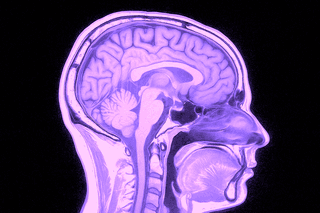

MR Hjärna – Magnetkameraundersökning vid neurologiska symtom eller misstänkta förändringar i hjärnan

Magnetkameraundersökning av hjärnan (magnetröntgen) är en central metod inom neurologisk diagnostik. Den används vid en rad symtom som kan indikera sjukliga förändringar i hjärnvävnad, blodkärl eller nervbanor – exempelvis återkommande huvudvärk, yrsel, synrubbningar, domningar, kognitiva störningar eller minnesproblematik.

Undersökningen ger högupplösta tvärsnittsbilder av hjärnans vävnad, ventrikelsystem, kärl och kranialnerver. MR används både vid akuta insjuknanden (t.ex. stroke eller plötslig medvetandepåverkan) och vid planerad utredning av mer långvariga eller diffusa symtom. Den är även värdefull för uppföljning av tidigare fynd såsom cystor, aneurysm eller tumörer, samt vid misstanke om neurodegenerativa sjukdomar som multipel skleros, Parkinsons sjukdom eller olika former av demens.

En MR-undersökning av hjärnan tar cirka 20–30 minuter och är helt smärtfri. Du ligger stilla i en magnetkamera som tar tvärsnittsbilder av hjärnans strukturer. Undersökningen sker utan remiss från vårdcentral – vi utfärdar den direkt i samband med din bokning. Resultatet granskas av specialistläkare i neuroradiologi och du får ett skriftligt utlåtande inom några dagar.